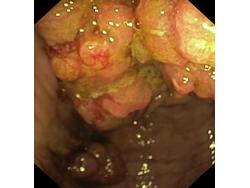

Nowotwory przewodu pokarmowego